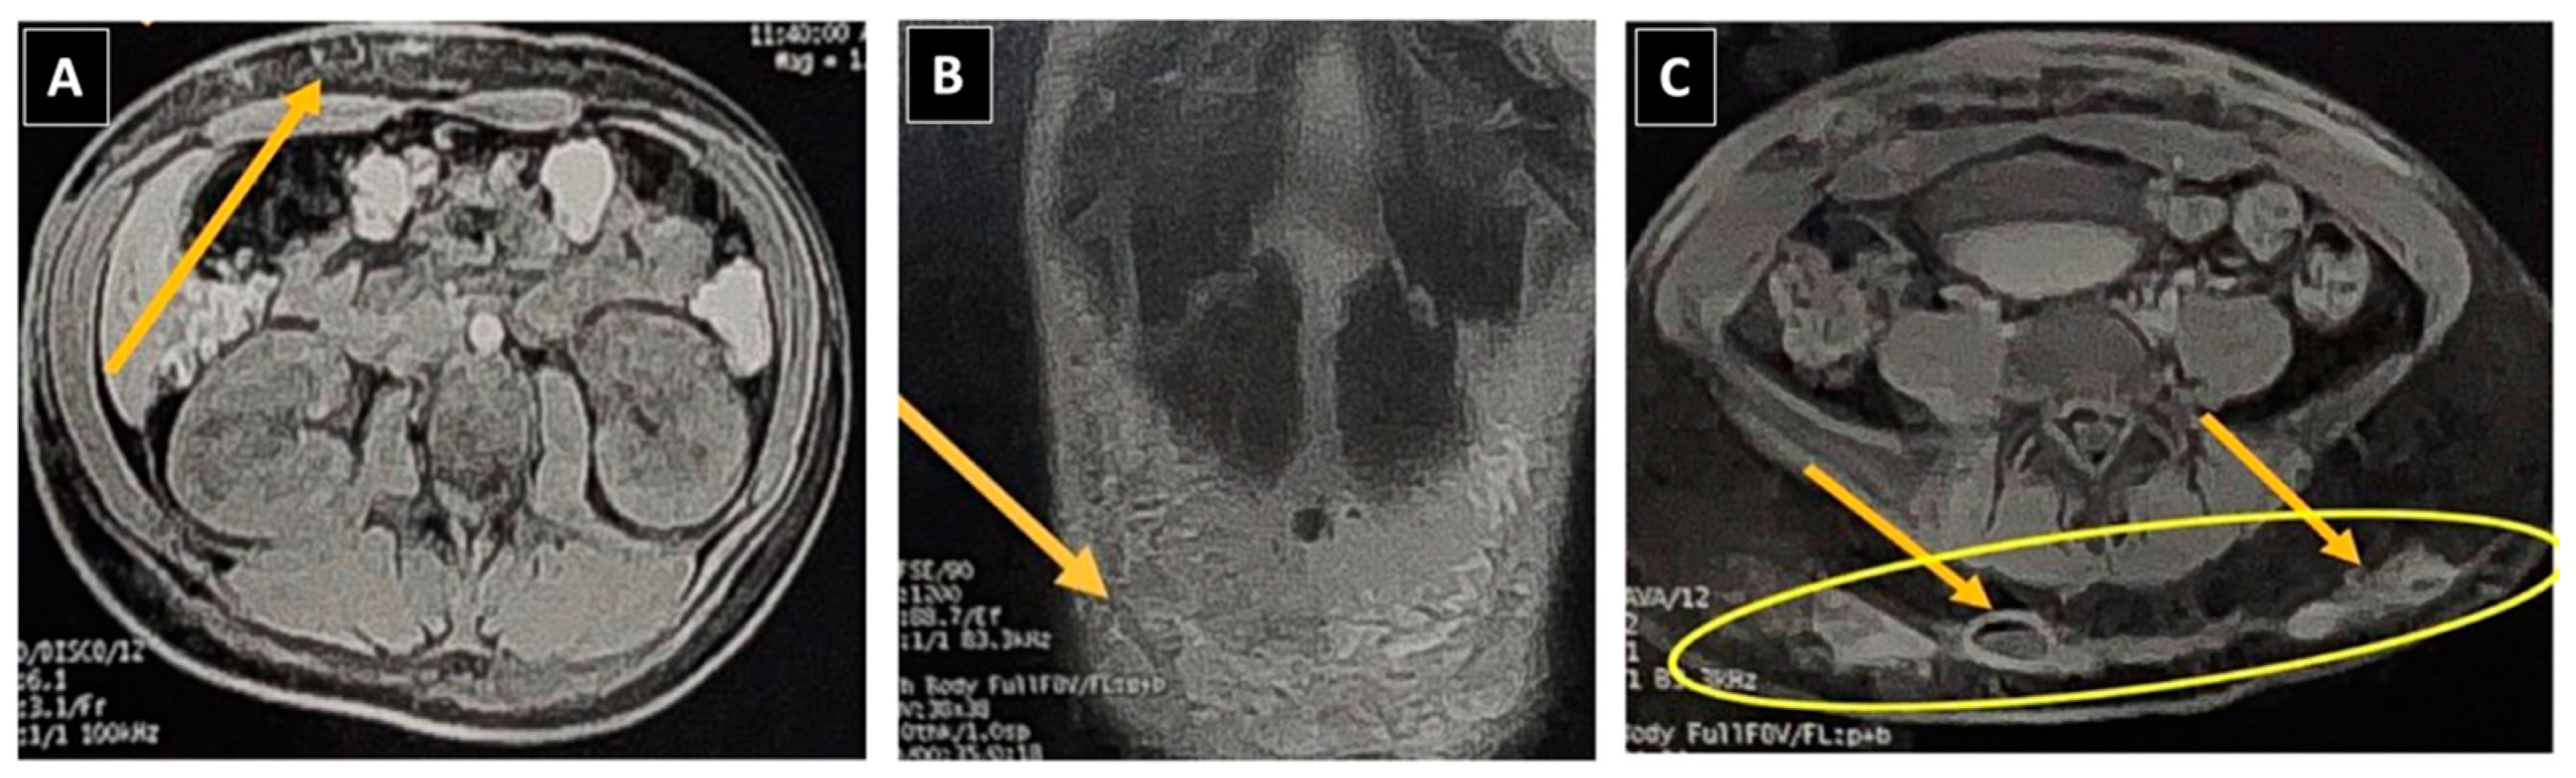

After a year and a month of medication, a new surgical procedure was performed to remove residual nodules and fibrotic areas (Figure 3) identified via abdominal wall ultrasound, indicating the persistence of two adjacent residual subcutaneous nodules measuring 0.8 × 0.5 × 0.6 cm and 1.5 × 0.9 × 0.6 cm. They appeared hypoechoic with internal areas of higher echogenicity, regular contours, and no significant flow on Doppler, suggesting remaining infectious foci. Twenty days post-procedure and after 1 year and 2 months of treatment (still on Clofazimine, Moxifloxacin, and Clarithromycin), the patient remains well, without new abscesses, with treatment scheduled to conclude in January 2024.

Figure 3. Progression of lesions caused by Mycobacterium abscessus after lipolytic enzyme application. (A) Nodular lesion featuring an erythematous base situated in the right upper quadrant of the abdomen. (B) Scars with subcutaneous nodules shown on ultrasound. (C) Scars post-surgical excision of the nodules.